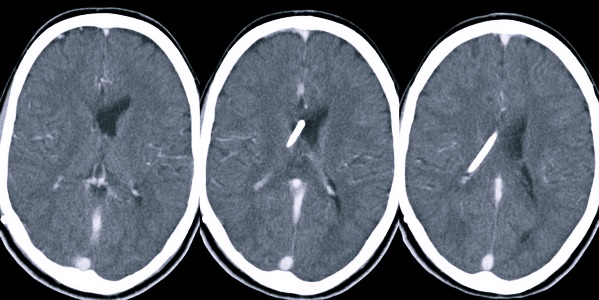

Подтвердить наличие асимметрии боковых желудочков можно, пройдя компьютерную томографию, магнитно-резонансную томографию, нейросонограмму, офтальмологическое обследование глазного дна, пункцию ликворной жидкости.

Нарушается отток цереброспинальной жидкости при перекрытии ликворного пути опухолевидным новообразованием или кистой. Расширение боковых желудочков происходит на фоне травмирования головы, развития идиопатической гидроцефалии, присутствия посттравматической гематомы. Также расширение структур может быть вызвано геморрагическим инсультом, тромбозом центрального сосуда.

Асимметрия боковых желудочков головного мозга может проявляться различными неврологическими симптомами, включая головные боли, нарушения координации, проблемы с памятью и вниманием. Врачи отмечают, что данное состояние может быть связано с различными патологиями, такими как травмы головы, инсульты или врожденные аномалии. Для диагностики асимметрии используются методы нейровизуализации, такие как МРТ, которые позволяют точно оценить размеры и форму желудочков.